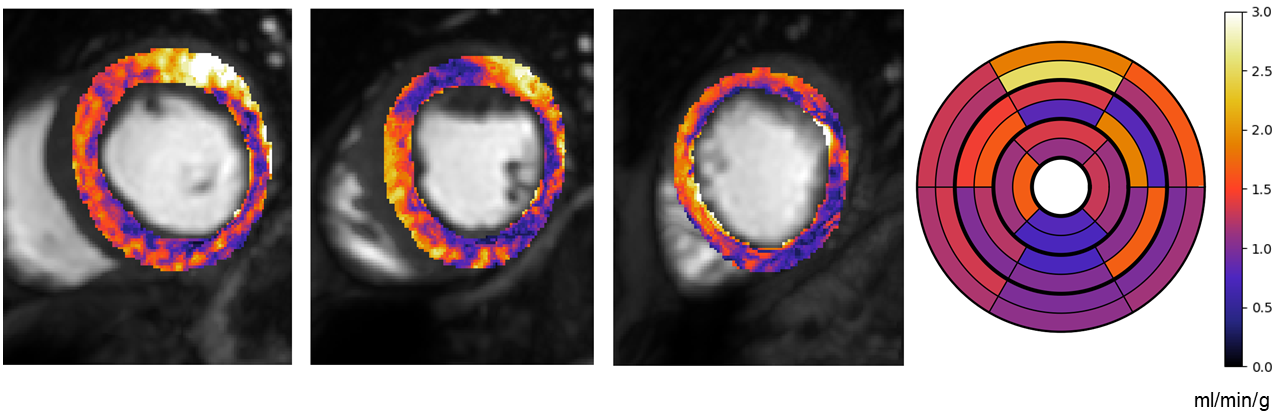

\printthesisindex